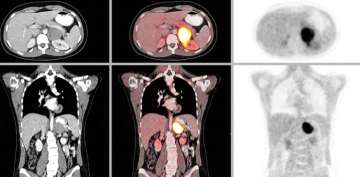

CT or MRI of the abdomen will almost always identify a pheochromocytoma. Additional specialized imaging such as MIBG (meta-iodobenzylguanidine) or Ga-68 Dotatate PET/CT scan can help to confirm a pheochromocytoma and identify multiple tumors or metastatic spread.